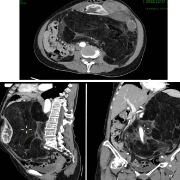

入院后,该患者行CT示左侧腹膜后巨大肿瘤,大小约40 cm x30 cm x25cm,肿瘤紧邻主动脉、下腔静脉、腹腔干、肠系膜上动脉等重要血管,脾动静脉、左肾、左肾动静脉、左输尿管已经被肿瘤包裹并明显移位向前贴近腹壁,脾脏、胰体尾部、肾脏明显受压变形特别是左肾明显变小,小肠及系膜已经明显受压挤至右外侧,左半结肠明显受压,导致病情十分复杂,若手术将极易损伤上述重要血管和脏器,因此手术难度极大、风险极高。